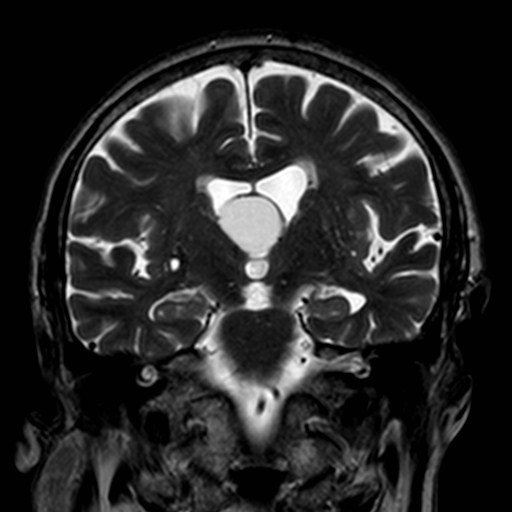

Esta imagen de resonancia pertenece a un paciente de edad media que comenzó con cefalea brusca con los movimientos cefálicos. La aparición de la cefalea en un paciente «de novo», la edad de aparición y las características de la misma me llevaron a solicitar una prueba de imagen que reveló el quiste del 3º ventrículo de la imagen de resonancia cerebral.

Su localización es típicamente en el techo del 3º ventrículo entre ambos forámenes de Monro y los pilares anteriores del trígono.